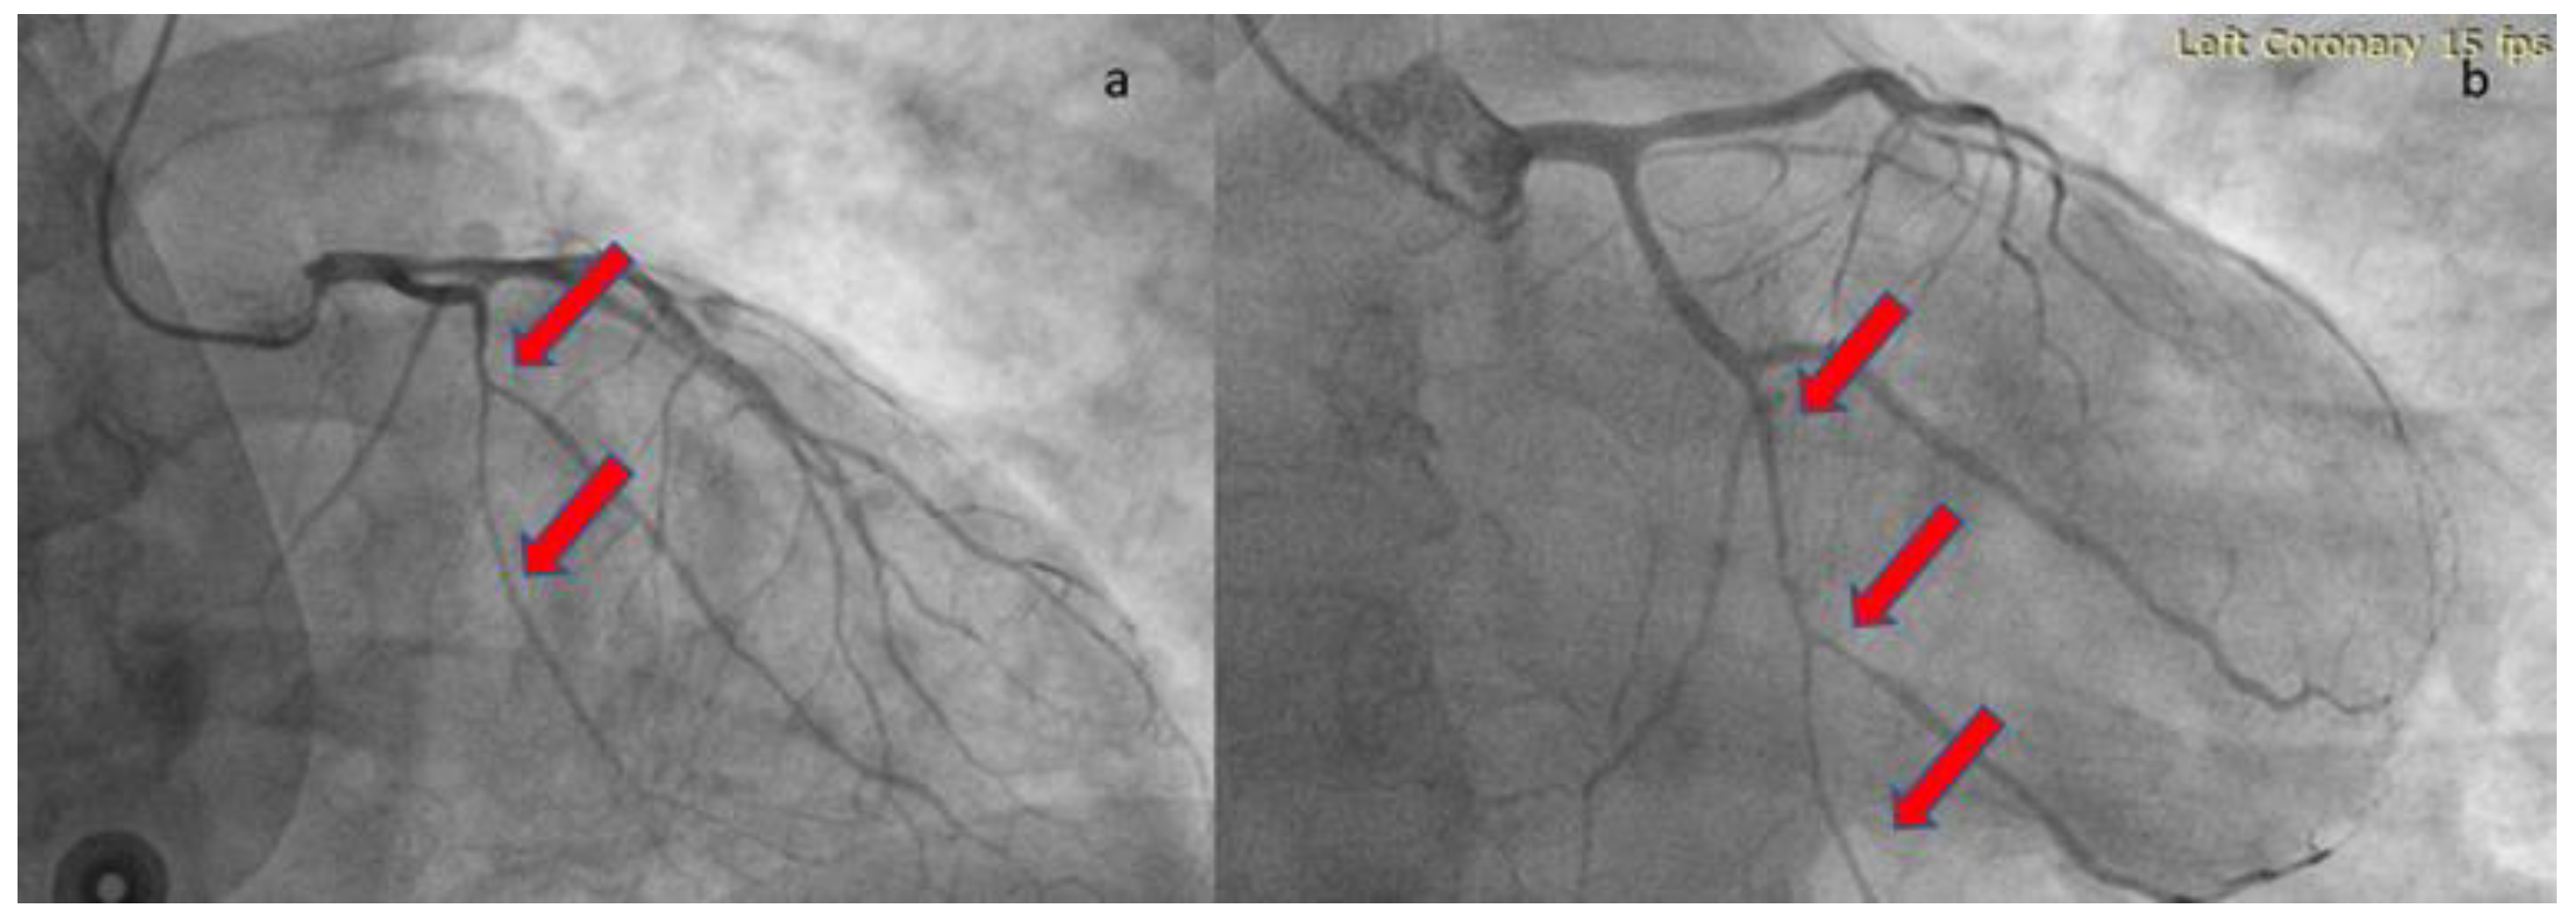

A 51-year-old Caucasian male, with a medical history of hypertension was admitted to our hospital’s COVID-19 clinic, due to recent onset of fever, cough, and respiratory distress along with positive real-time polymerase chain reaction assay for SARS-CoV-2 infection. He was initially administered with oxygen via high-flow-nasal-cannula, dexamethasone, remdesivir, tocilizumab bolus and fondaparinux for thromboprophylaxis. On day-7, while in severe respiratory distress (Figure 1) supported with continuous positive airway pressure-helmet, the patient complained of retrosternal chest pain, radiating in his left arm with concomitant diaphoresis. His blood pressure was 140/80mmHg and his pulse was 55 beats per minute. Lung auscultation revealed rales in both lungs, while the rest of the physical exam was normal. An electrocardiogram (ECG) was immediately obtained, which demonstrated normal sinus rhythm and 2mm ST-segment elevation in leads II, III, AVF, V5, V6 along with ST-segment depression in leads V1-V2.

Figure 1. Chest x-ray on the day of the episode.